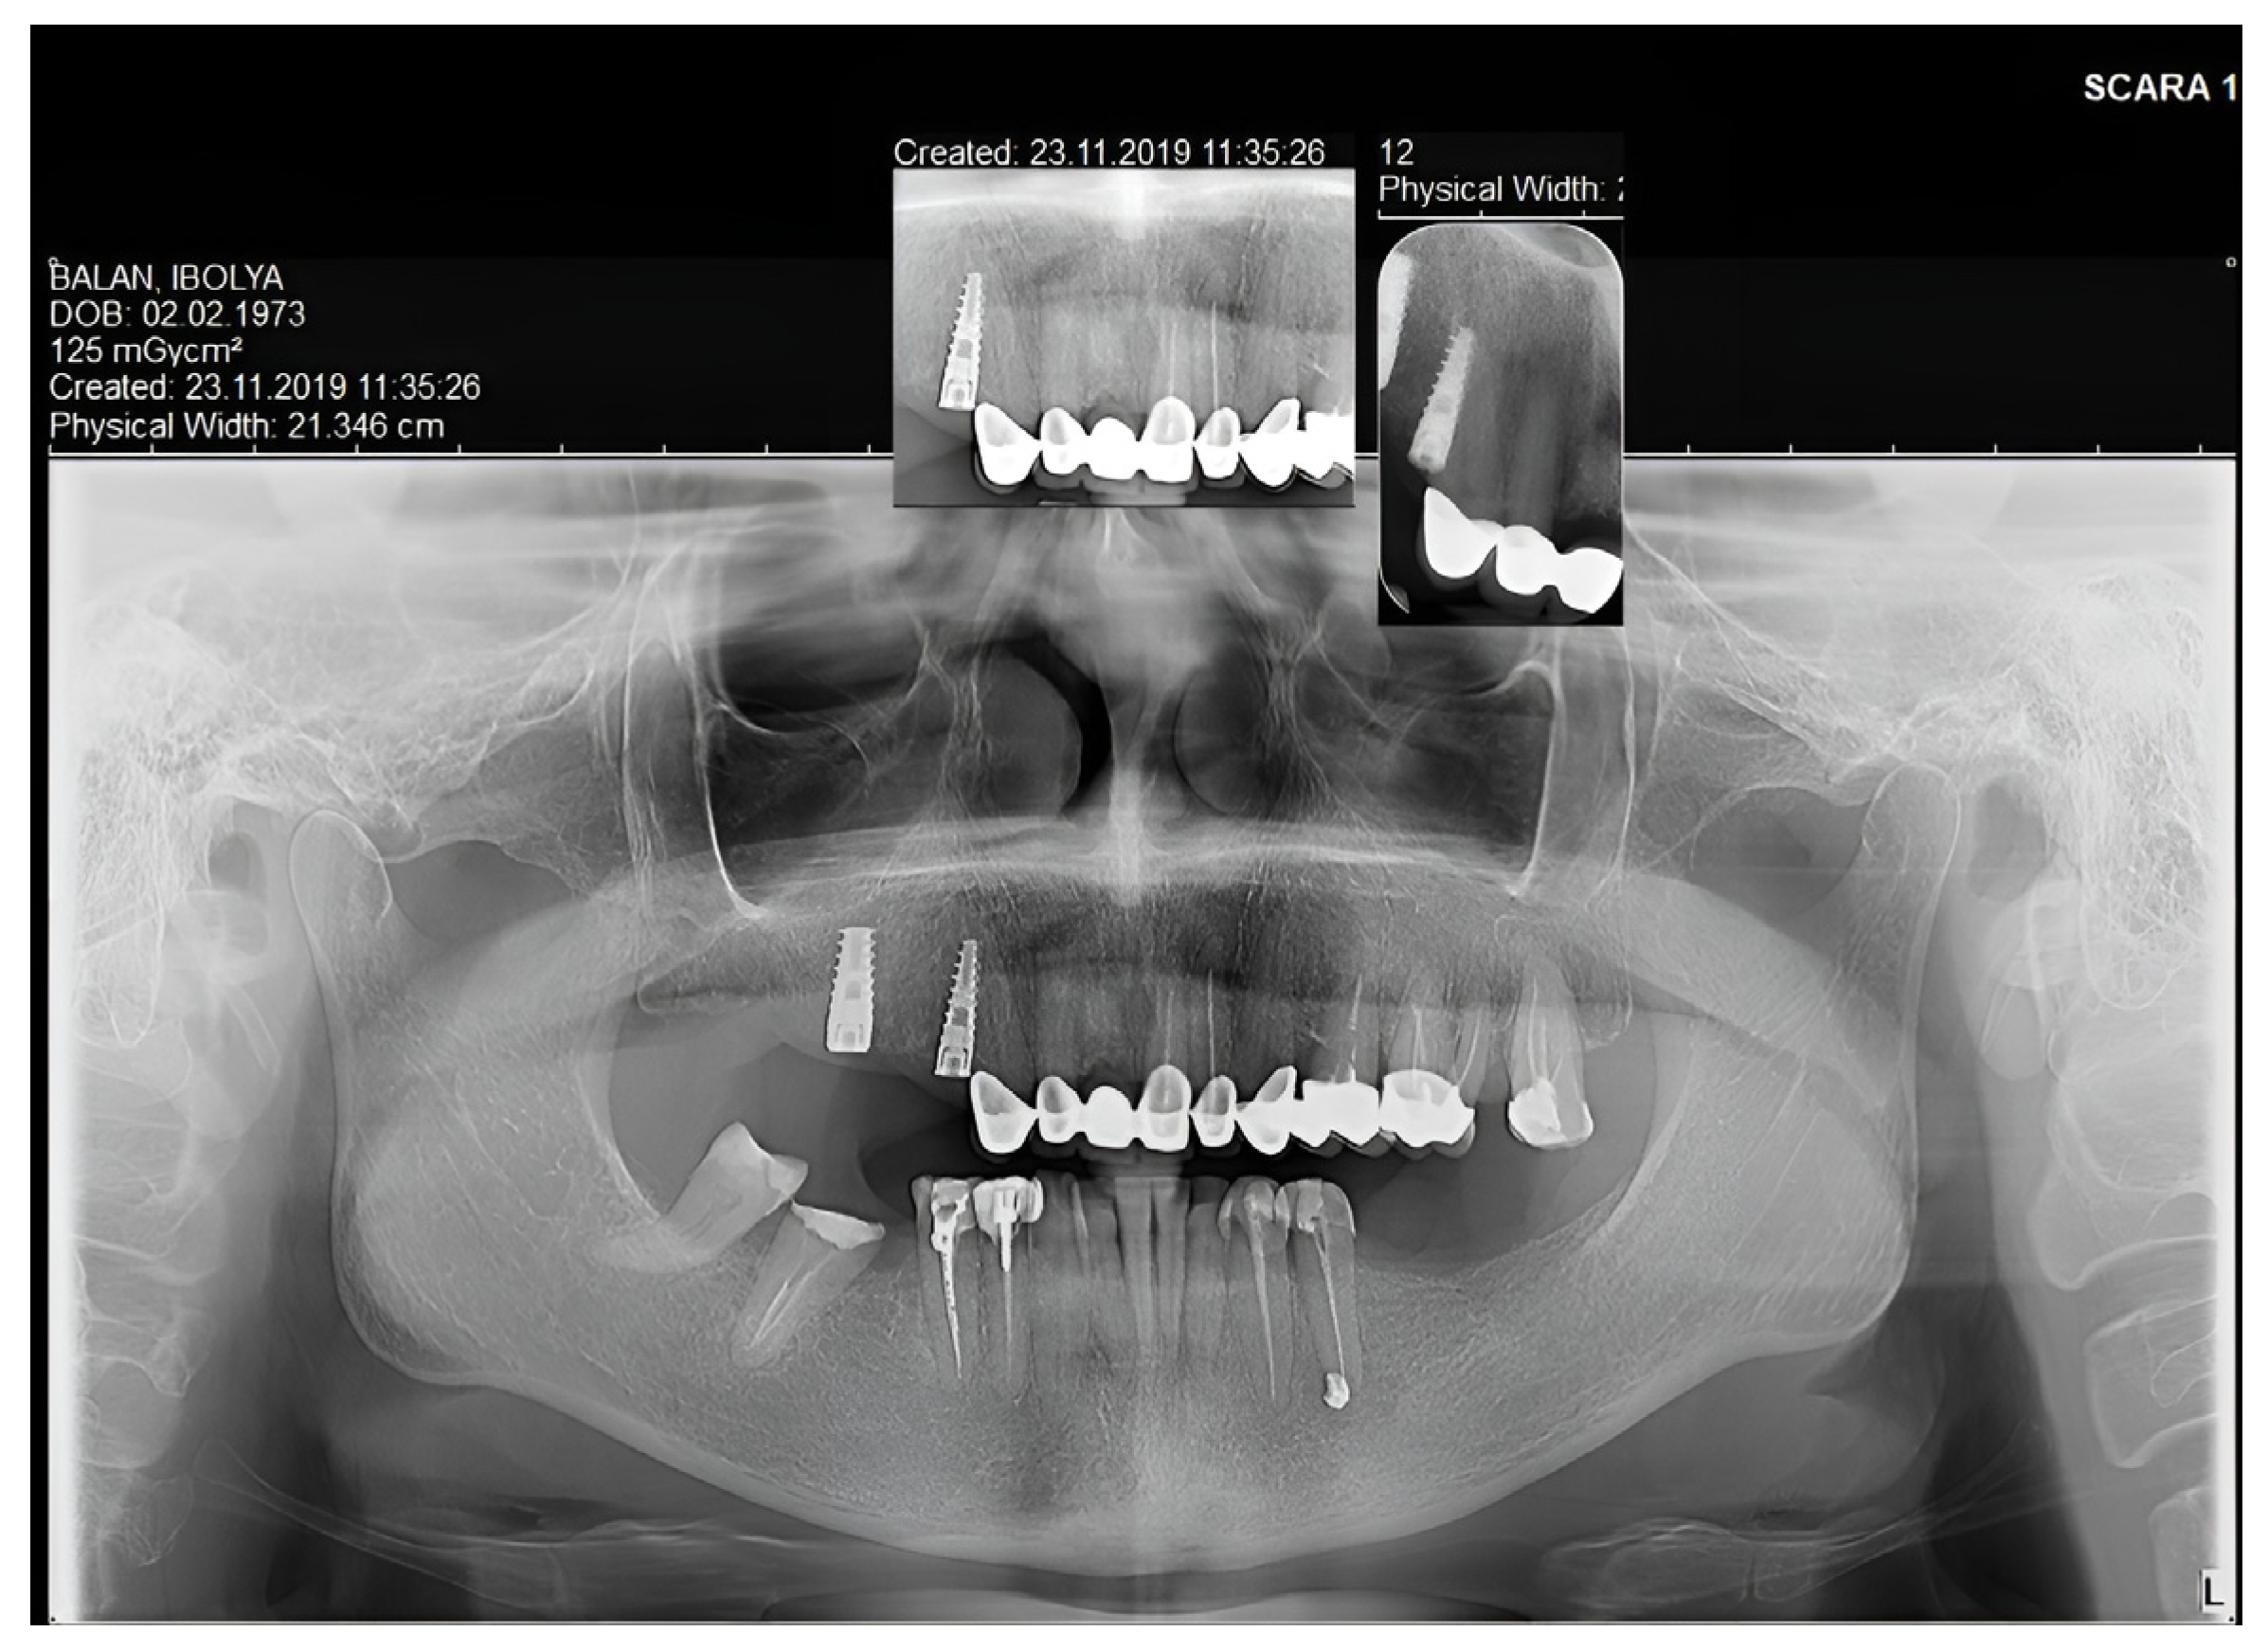

2. Case Report